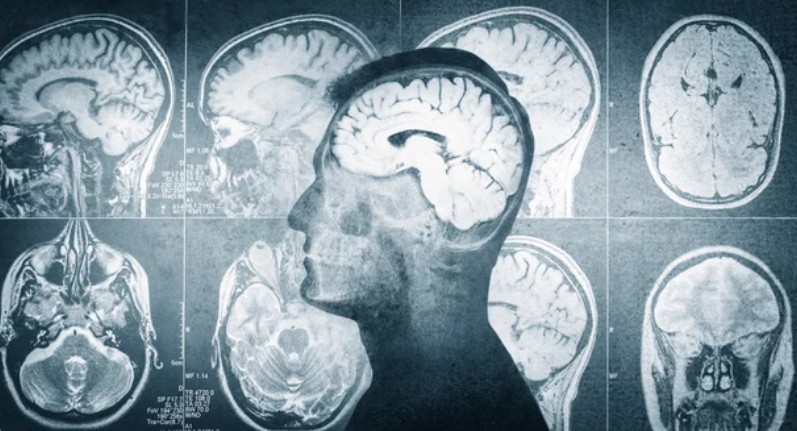

Medical imaging plays a critical role in modern healthcare, enabling doctors to diagnose diseases, guide treatments, and monitor patient progress with precision. Among the many imaging technologies available, Magnetic Resonance Imaging (MRI) stands apart from radiation-based methods such as X-rays, CT scans, and nuclear imaging. Patients often hear these tests grouped together, which can create confusion—especially regarding safety and long-term health risks.

What Is Magnetic Resonance Imaging (MRI)?

MRI does not use ionizing radiation. Instead, it relies on the natural magnetic properties of hydrogen atoms in the body to generate detailed images, particularly of soft tissues.

How MRI Produces Images Without Radiation

Superior Soft Tissue Contrast

MRI excels at imaging soft tissues such as:

• Brain and spinal cord

• Muscles and ligaments

• Organs like the liver and prostate

• Tumors and inflammation